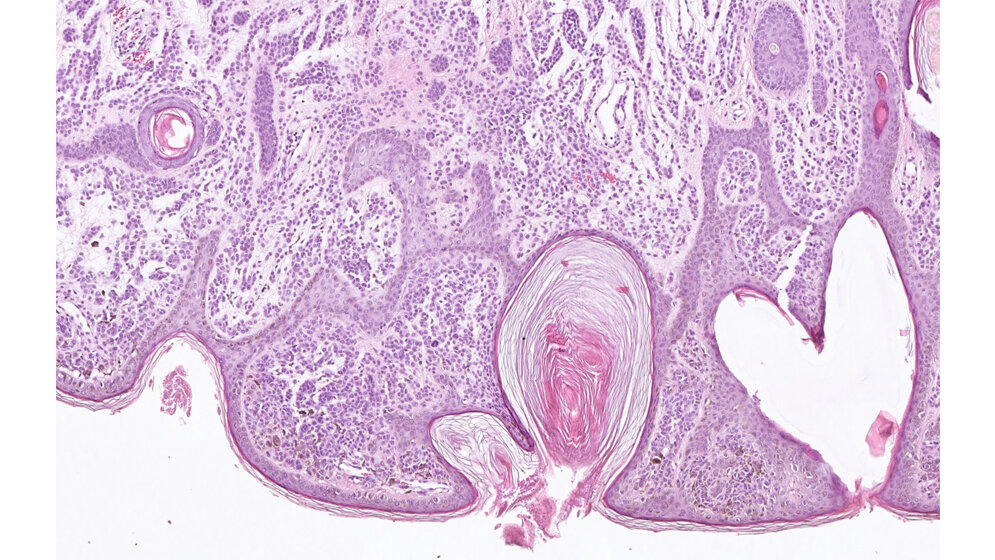

Der schwarze Hautkrebs, das sogenannte maligne Melanom, ist für den Großteil der Hautkrebs-bedingten Todesfälle verantwortlich. Nach wie vor stellt bei Verdacht auf schwarzen Hautkrebs die Untersuchung einer Gewebeprobe den Goldstandard in der Diagnostik dar. Die Proben werden so gefärbt, dass sich verschiedene Gewebestrukturen im mikroskopischen Bild unterscheiden lassen. Das ermöglicht es dem erfahrenen Pathologen zu entscheiden, ob es sich um ein Melanom handeln könnte oder nicht.

Internationale Studien zeigen, dass zwei Pathologen bei der Entscheidung, ob es sich um ein gutartiges Muttermal oder einen schwarzen Hautkrebs handelt, in bis zu 26 Prozent der Fälle zu unterschiedlichen Ergebnissen gelangen. Heidelberger Wissenschaftler und Ärzte haben nun die diagnostische Qualität eines lernfähigen Algorithmus mit der Leistung von Pathologen verglichen. Für diese Untersuchung stellte das Institut für DermatoHistoPathologie Krahl in Heidelberg Proben zur Verfügung: Die 345 mit Melanom- und 350 mit Muttermalbiopsien beladenen anonymisierten Objektträger waren zuvor nach Leitlinie durch einen erfahrenen Pathologen klassifiziert worden. Anschließend wurden zufällig ausgewählte Bildausschnitte von 595 der 695 Objektträger für das Training des Algorithmus eingesetzt. Die übrigen 100 Bildausschnitte – 50 Melanom versus 50 Muttermale – wurden verwendet, um die diagnostische Qualität des lernfähigen Algorithmus gegenüber dem Pathologen zu testen.